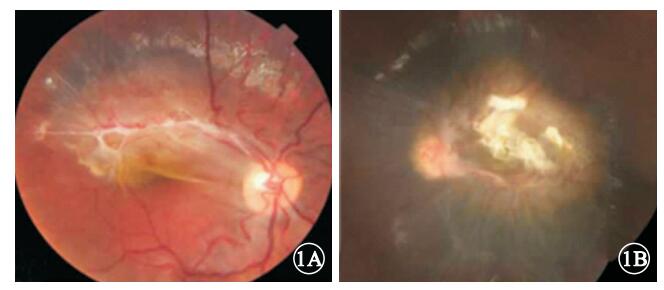

所有患眼的CHRRPE病灶均位于后極部,呈不同程度的黃白色隆起,其周圍深層視網膜均因色素沉著而呈灰黑色,瘤體表面有不同程度的灰白色纖維膜增生,視網膜因纖維膜牽引而呈現皺褶,視網膜血管呈螺旋樣紆曲向病變中央走行(圖 1);均無出血及滲出。8只眼中,累及黃斑和視盤3只眼,占37.5%;僅累及黃斑5只眼,占62.5%。

圖1

CHRRPE患眼彩色眼底像。1A. 9歲患兒右眼彩色眼底像;1B. 21歲患者左眼彩色眼底像。黃斑區有黃白色隆起病灶,其附近深層視網膜色素沉著,病灶表面有視網膜前纖維膜與視盤相連,視網膜血管紆曲

圖1

CHRRPE患眼彩色眼底像。1A. 9歲患兒右眼彩色眼底像;1B. 21歲患者左眼彩色眼底像。黃斑區有黃白色隆起病灶,其附近深層視網膜色素沉著,病灶表面有視網膜前纖維膜與視盤相連,視網膜血管紆曲

所有患眼的CHRRPE病灶均位于后極部,呈不同程度的黃白色隆起,其周圍深層視網膜均因色素沉著而呈灰黑色,瘤體表面有不同程度的灰白色纖維膜增生,視網膜因纖維膜牽引而呈現皺褶,視網膜血管呈螺旋樣紆曲向病變中央走行(圖 1);均無出血及滲出。8只眼中,累及黃斑和視盤3只眼,占37.5%;僅累及黃斑5只眼,占62.5%。

圖1

CHRRPE患眼彩色眼底像。1A. 9歲患兒右眼彩色眼底像;1B. 21歲患者左眼彩色眼底像。黃斑區有黃白色隆起病灶,其附近深層視網膜色素沉著,病灶表面有視網膜前纖維膜與視盤相連,視網膜血管紆曲

圖1

CHRRPE患眼彩色眼底像。1A. 9歲患兒右眼彩色眼底像;1B. 21歲患者左眼彩色眼底像。黃斑區有黃白色隆起病灶,其附近深層視網膜色素沉著,病灶表面有視網膜前纖維膜與視盤相連,視網膜血管紆曲